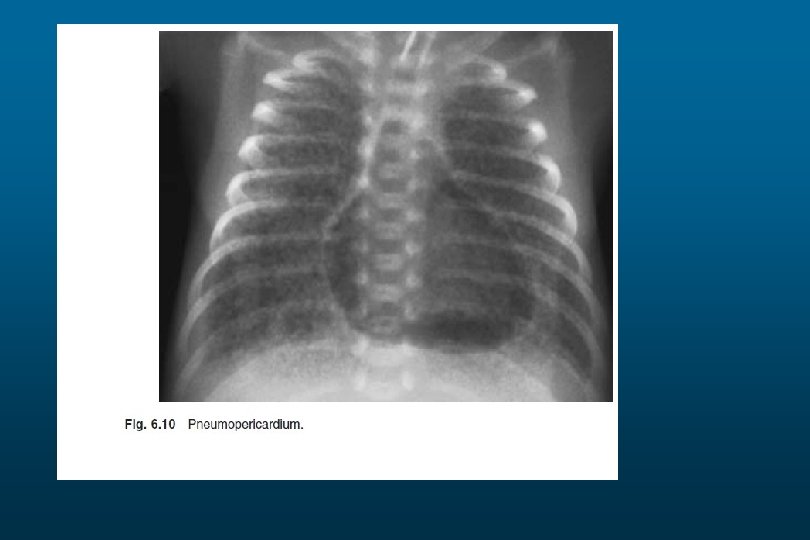

RDS